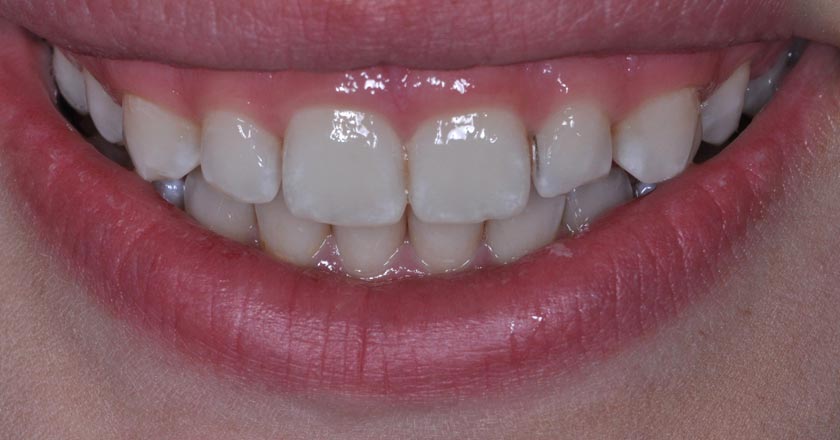

Gummy Smile - Before And After

Gummy smile correction – before treatment 2

Gummy smile correction – after treatment 2